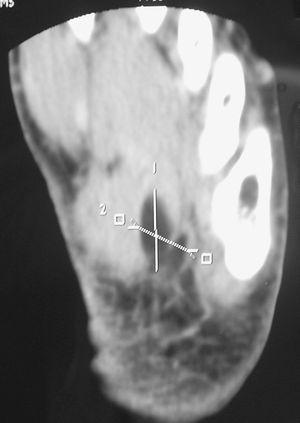

Mujer con dolor y tumoración en el arco plantar del pie izquierdo

Contreras Blasco

Rev Esp Enferm Metab Oseas 2007;16:84

Acceso a texto completo